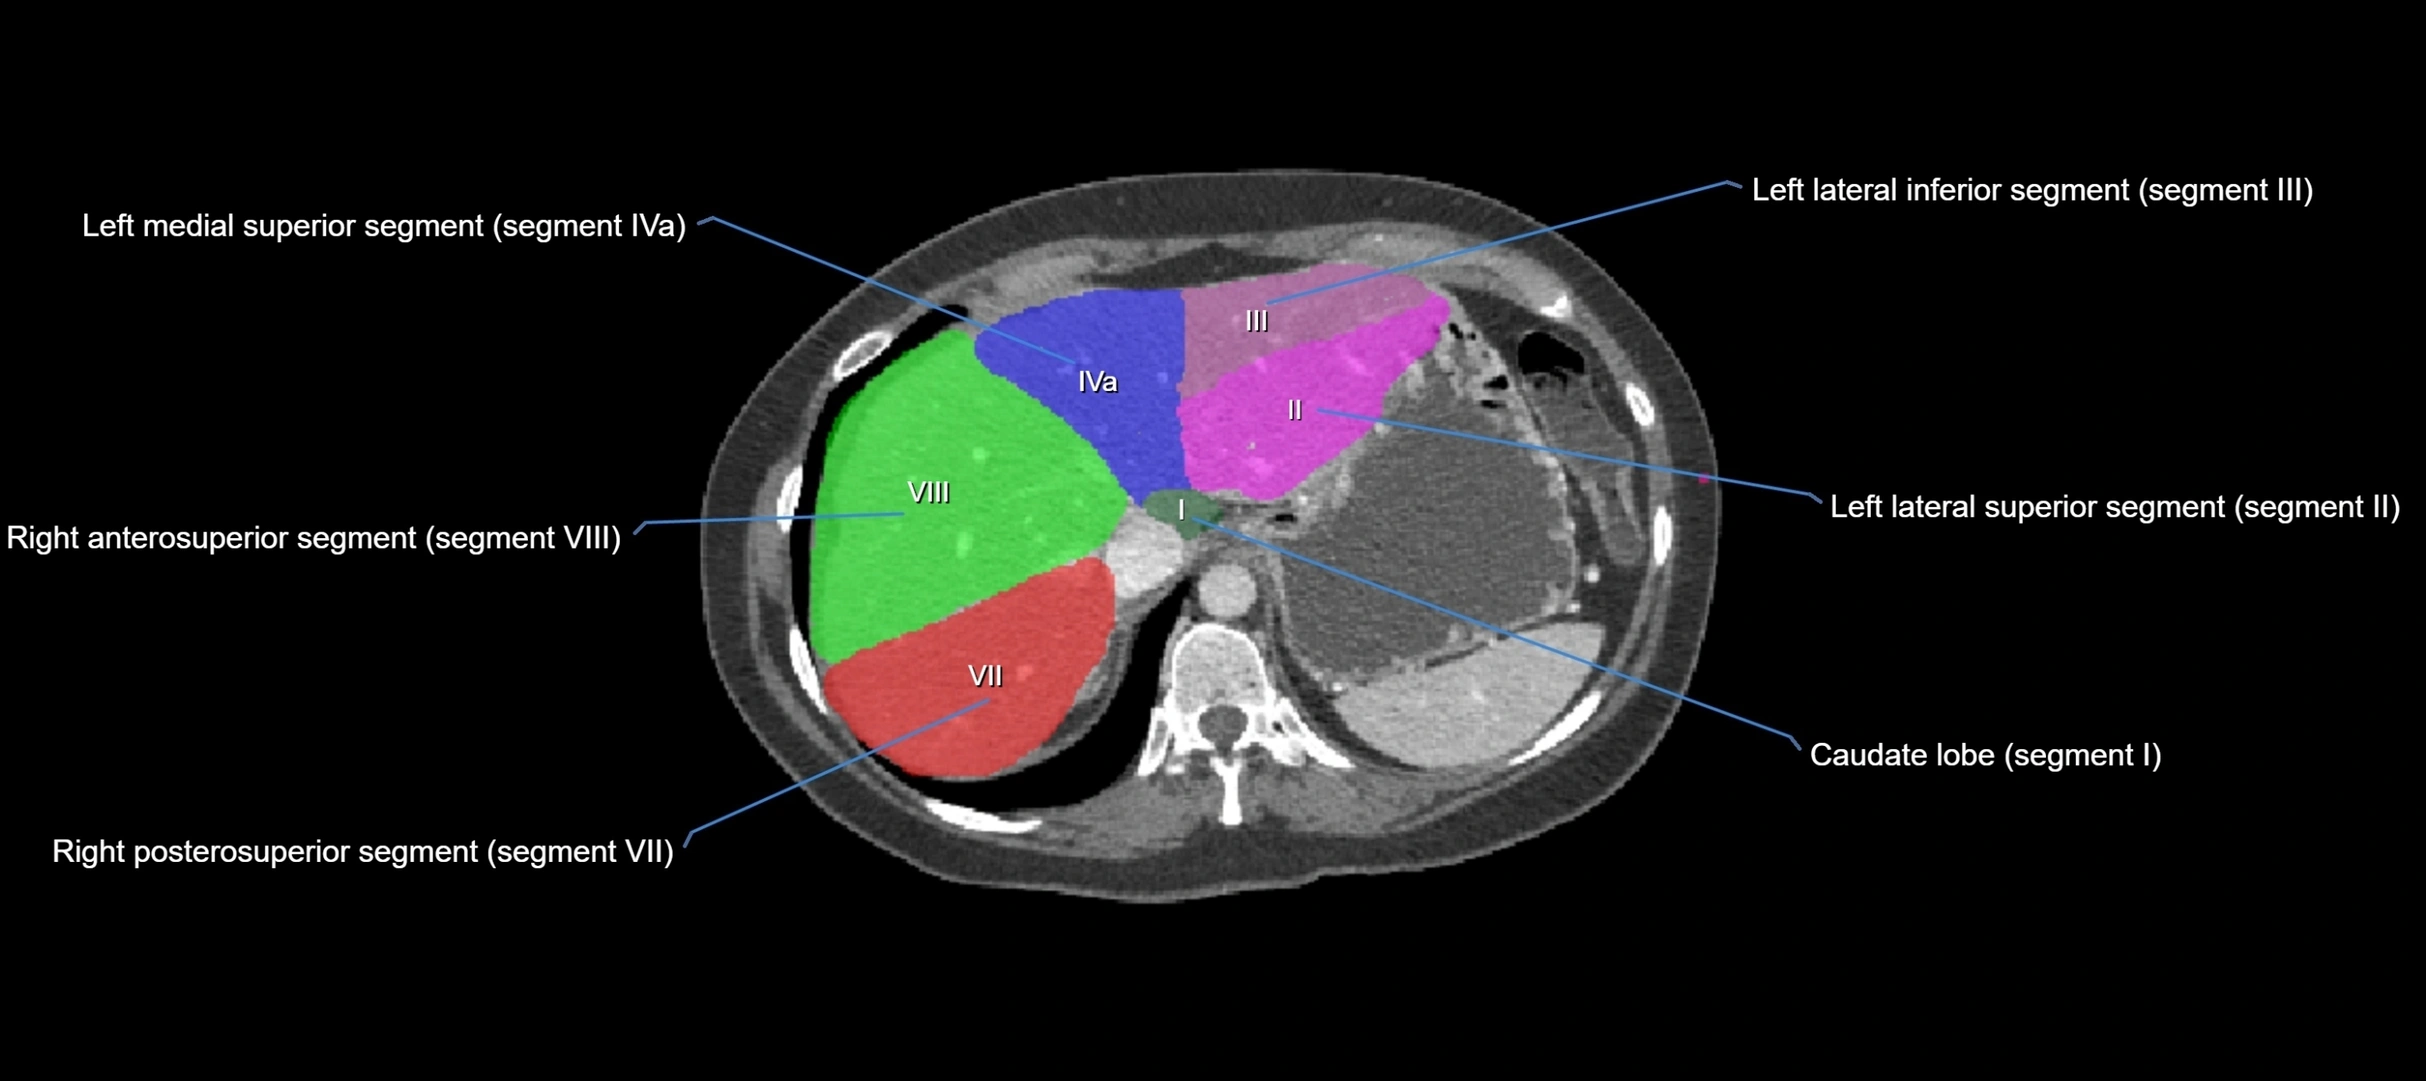

The caudate lobe of the liver is a distinct anatomical subdivision of the liver, designated as segment I in Couinaud’s classification. It lies on the posterior surface of the liver, between the fissure for the ligamentum venosum (left boundary) and the groove for the inferior vena cava (IVC) (right boundary). Superiorly, it is related to the posterior liver surface, and inferiorly it is separated from the left lobe by the porta hepatis.

The caudate lobe is unique because it receives dual portal venous and arterial inflow from both the right and left portal veins and hepatic arteries. It also has independent venous drainage directly into the IVC via multiple small hepatic veins, unlike other lobes that drain through the three main hepatic veins.

This anatomical autonomy makes the caudate lobe especially significant in liver surgery, transplantation, and hepatic venous outflow obstruction syndromes (e.g., Budd–Chiari syndrome). Enlargement of the caudate lobe is a characteristic imaging feature in chronic liver disease and cirrhosis.